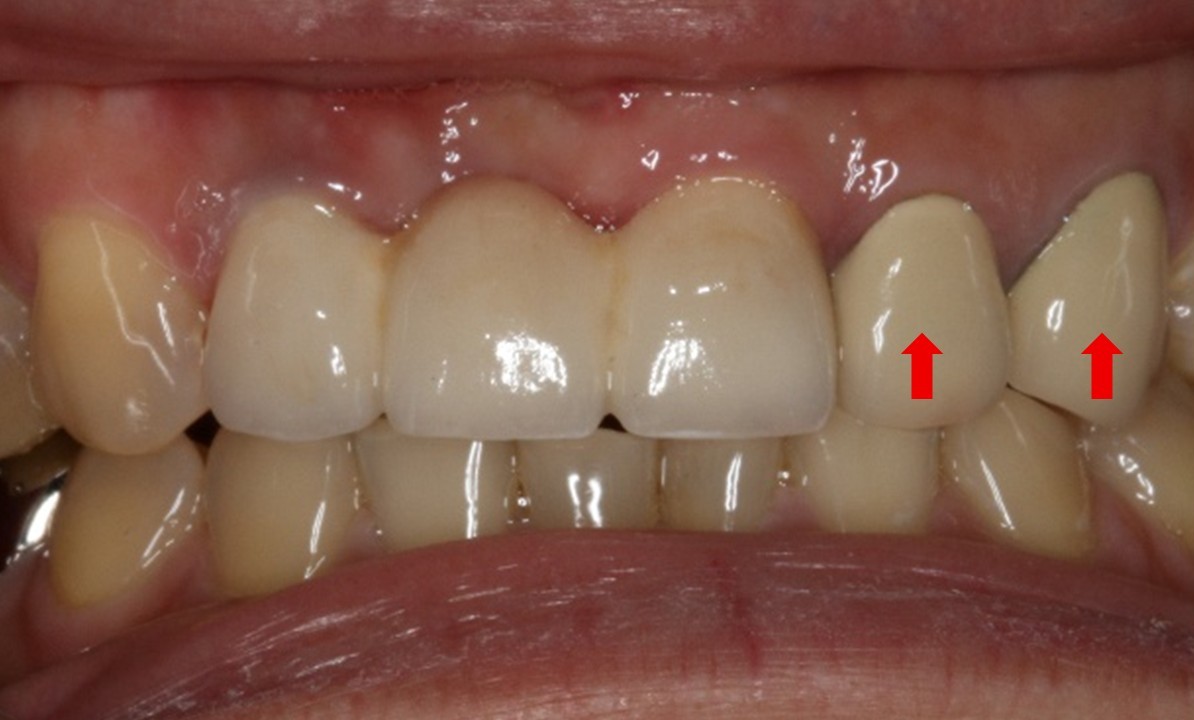

因牙齦萎縮而露出金屬邊緣的黑線-蒔雨牙醫診所

因牙齦萎縮而露出金屬邊緣的黑線